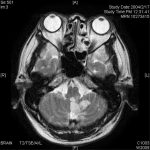

正確に言うと、脳卒中は病名ではありません。脳の血管が詰まって流れなくなったり、脳の血管が破れたりすることによって、脳の血流が障害される状態の総称のことです。具体的な病名だと、脳の血管が詰まる「脳梗塞」、脳の血管が破れる「脳出血」や「くも膜下出血」が脳卒中にあたります。

脳梗塞は、脳の血管が狭くなったり、詰まったりして、脳に血液が流れなくなる状態です。血液は酸素や栄養などを脳に運ぶ役割がありますが、血流が滞るとその先の脳が機能しなくなってしまうのです。脳梗塞の原因は、いわゆる「血液ドロドロ」や血液を押し出すポンプである心臓の疾患などがあります。詰まった血管の場所や太さによって、意識障害や片麻痺、感覚障害や言語障害などの様々な症状が起こります。

脳出血は脳の中で血管が破れて出血してしまった状態で、原因は高血圧が最も多いですね。症状は出血の部位によって異なりますが、突然起こる頭痛や意識障害などが高頻度にみられます。

くも膜下出血は、脳の表面近くにある血管が破れることによって、脳を覆っている「くも膜」と脳の間に出血してしまった状態のことです。原因としては、「脳動脈瘤(のうどうみゃくりゅう)」という脳の動脈にあるコブが裂けて出血する場合が最も多いとされています。くも膜下出血の主な症状は、頭痛、意識障害、嘔吐で、重症化しやすい傾向にあります。